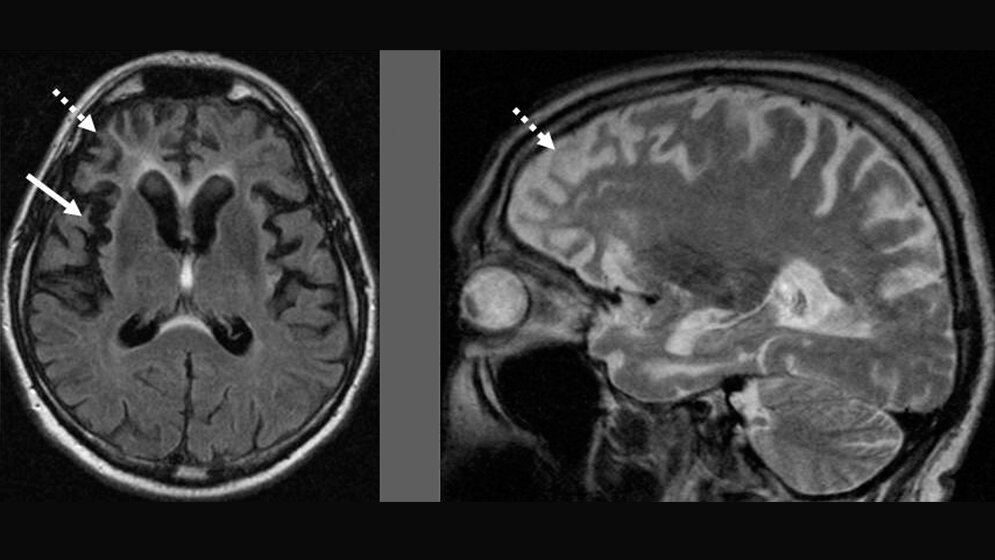

Die beteiligten Gene haben Einfluss auf Signalwege im Inneren der Nervenzellen. Je nach Gen handelt es sich um einen anderen Weg mit anderen Auswirkungen. „Was die Genfehler eint, ist, dass sie alle letztendlich dazu führen, dass Nervenzellen im Stirn- und Schläfenbereich des Gehirns absterben“, erklärt Mitautor Professor Dr. Peter Heutink. „Das Gute jedoch ist: Wir glauben, dass wir künftig in einige der Signalwege eingreifen und dadurch die Krankheit verlangsamen können.“ Ausschlaggebend ist, dass der Arzt weiß, welches Gen und Signalweg beim jeweiligen Patient betroffen ist. „Für die Diagnostik und zukünftig die individualisierte Therapie der Frontotemporalen Demenz sollte daher die Untersuchung des gesamten Erbguts an erster Stelle stehen.“ (idw, red)